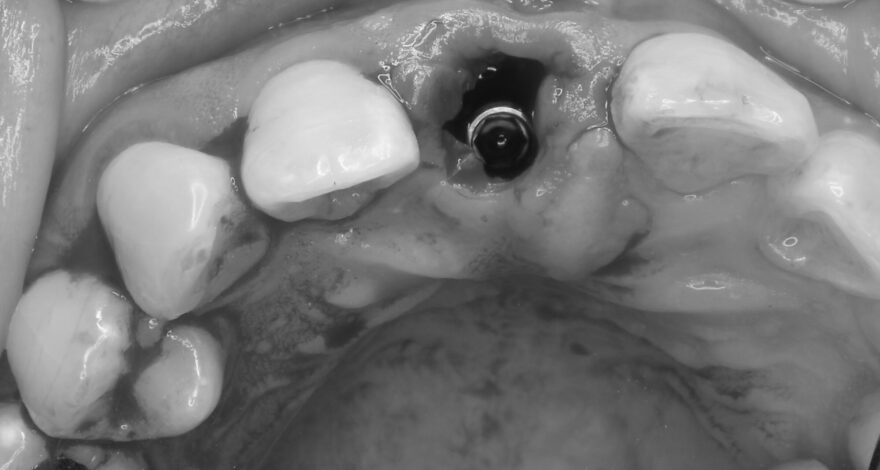

オペ中の口腔内写真とCT写真